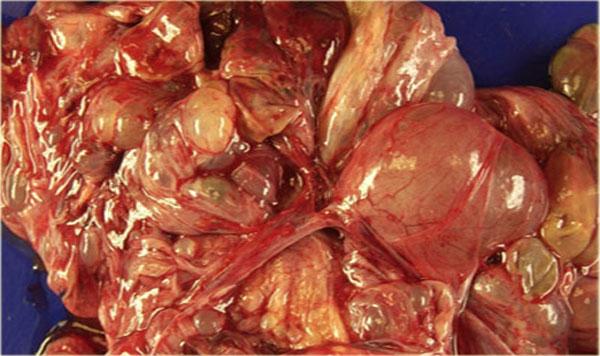

Di căn dạng nang đến buồng trứng

Mặc dù di căn đến buồng trứng thường có dạng đặc – chẳng hạn như di căn Krukenberg – di căn buồng trứng dạng nang vẫn có thể xảy ra.

Hình CT cho thấy các khối nang phức tạp ở cả hai buồng trứng.

Mặc dù ung thư biểu mô tuyến nang thanh dịch có thể xuất hiện hai bên, nhưng loại này thường có dạng đơn thùy hơn là đa thùy.

Hầu như không nhìn thấy một phần của ung thư đại trực tràng dạng vòng nhẫn (mũi tên xanh).

Nhìn thấy rõ ràng là các tổn thương cấy ghép dạng nang trên phúc mạc phản chiếu (mũi tên đỏ).

Đây là các tổn thương di căn buồng trứng dạng nang của ung thư đại trực tràng.

Đây là một đặc điểm hình ảnh không thường gặp.